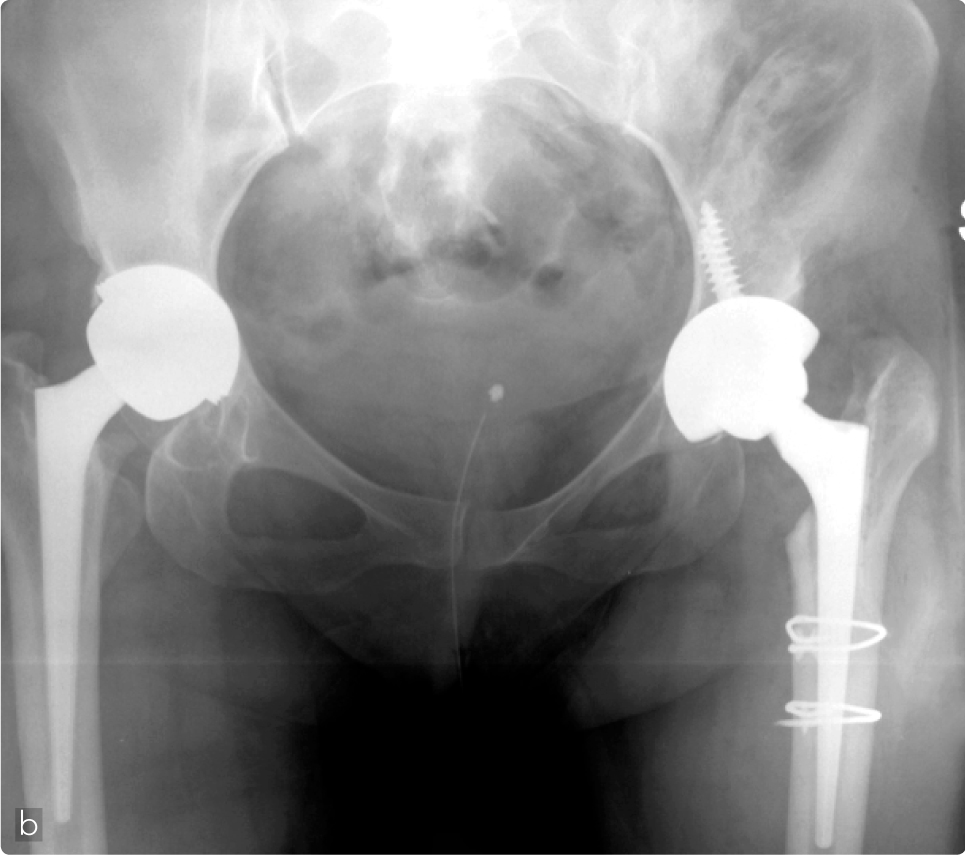

Femmina, 29 anni, affetta da grave coxartrosi secondaria a displasia congenita dell’anca con notevole accorciamento dell’arto (a). L’anca controlaterale affetta da una forma meno grave di displasia era già stata trattata con un impianto protesico. La componente acetabolare emisferica è stata impiantata nel paleocotile per ottenere la migliore biomeccanica articolare e ripristinare la corretta lunghezza degli arti inferiori. La patologica assenza della parete anteriore dell’acetabolo ha indotto ad utilizzare una componente emisferica a press-fit in tantalio che è stata stabilizzata ulteriormente con 2 viti posizionate in direzione della articolazione sacro-iliaca. Date le ridotte dimensioni del canale femorale e la patologica antiversione della regione meta-epifisaria del femore è stato deciso di impiegare una protesi conica che permettesse di correggere la deformità femorale senza necessità di osteotomie derotative. Nonostante sia stata impiegata la protesi con le dimensioni più piccole durante l'impianto dello stelo l'apertura di una crepa a livello del calcar ha richiesto l'applicazione di due cerchiaggi.

Ottimo il recupero funzionale ed il controllo radiografico a distanza di 6 mesi.